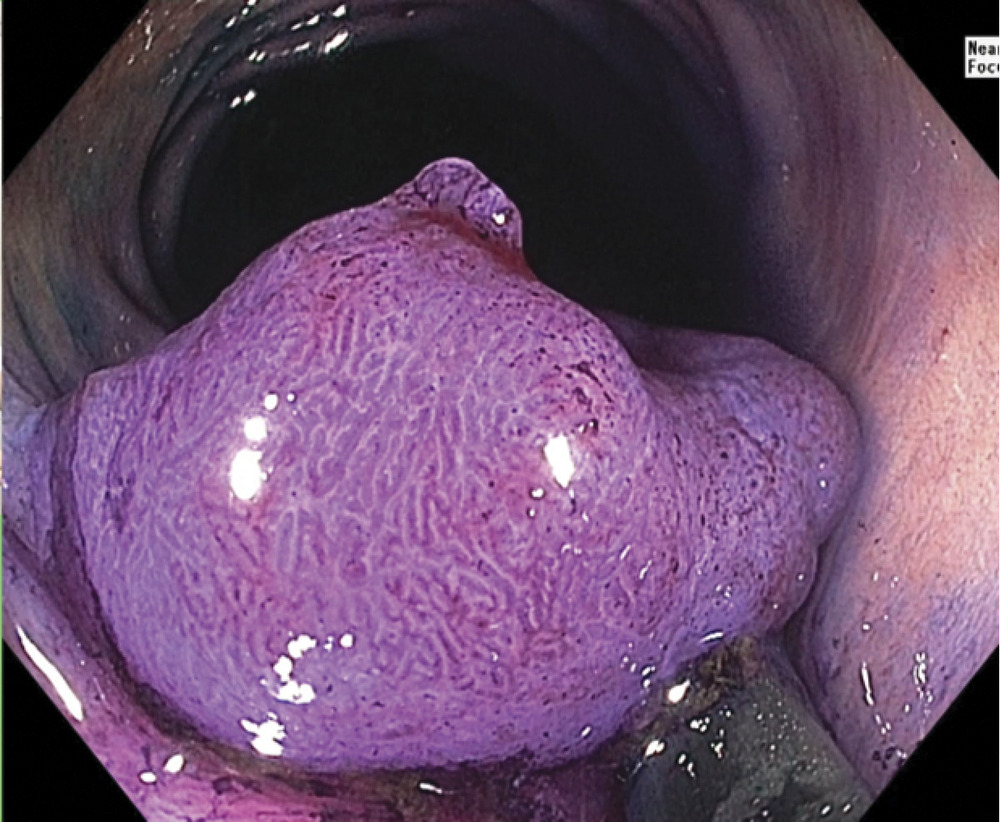

Исследование выполнялось при помощи видеоколоноскопа CF-HQ190L производства «Olympus» (Токио, Япония) и процессора серии EVIS Exera III. Эта система последнего поколения оснащена узкоспектральным режимом (NBI) и функцией увеличения изображения Near focus, которая позволяет выбрать нужную глубину резкости и получить более детализированное изображение слизистой оболочки и капиллярных сетей (рис. 3).

При проведении анализа поверхности проф. Ю. Сайто установил, что структура поверхности опухоли имеет тип Vi по классификации S. Kudo, что соответствует инвазии в глубокий подслизистый слой sm3 или мышечный слой стенки кишки. По современным стандартам, пациентке не было показано эндоскопическое удаление опухоли. Через 6 дней после проведения этапа дифференциальной диагностики глубины инвазии опухоли пациентке выполнена лапароскопическая резекция сигмовидной кишки, при которой было подтверждено наличие глубокой инвазии опухоли (рис. 5).

При проведении анализа проф. Ю. Сайто установил, что структура поверхности опухоли имеет тип IV по классификации S. Kudo, что соответствует инвазии только в поверхностный подслизистый слой sm1 (рис. 7).